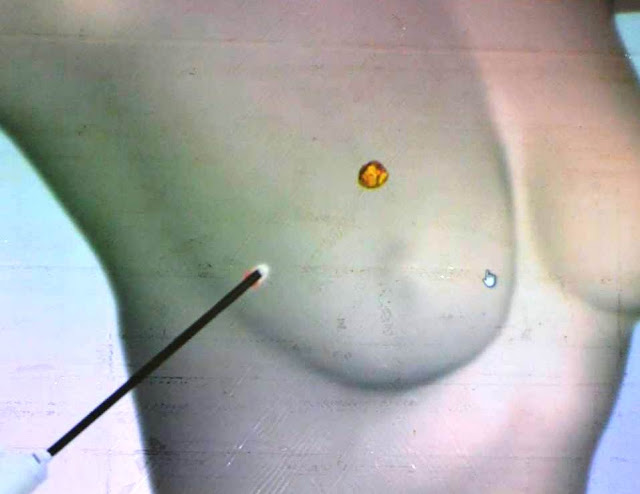

Ομιλητές ήταν ο Γιώργος Κυρόπουλος, ακτινολόγος – εξειδικευμένος στις παθήσεις μαστού και ο Χρήστος Βρέκας, χειρουργός μαστού.

- Δείτε εικόνες και βίντεο από την σημαντική εκδήλωση – ενημέρωση: